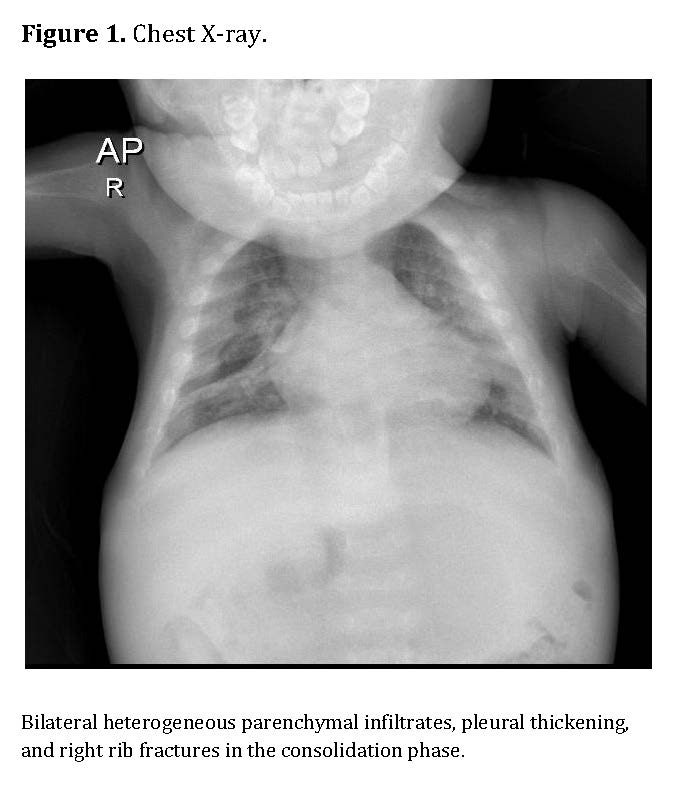

Chest radiography showed bilateral heterogeneous parenchymal infiltrates, pleural thickening, and right-sided rib fractures in the consolidation phase (Figure 1). Radiographs of long bones revealed severe osteopenia, periosteal reaction, and multiple pathological fractures, including the right and left humerus, right ulna, and right femur (Figures 2 and 3).